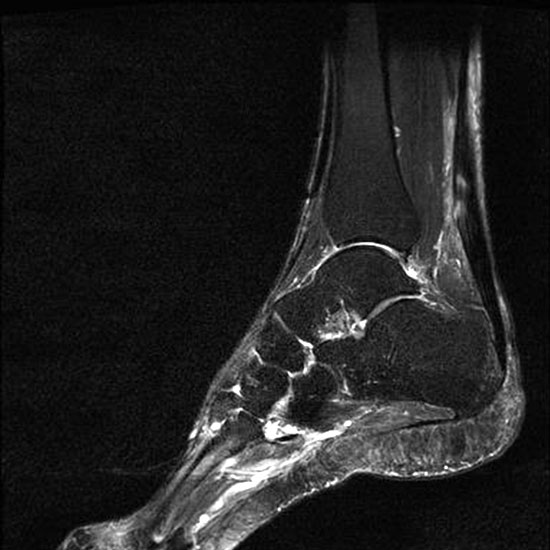

Hier befindet sich ca. 3-5 cm proximal des Tuber calcanei ein als „kritische Zone“ benannter Bezirk, der durch eine ungünstige arterielle Blutzufuhr gekennzeichnet ist (letzte Wiese). Hier finden sich häufig spindelförmige Schwellungen, die bei MRT-Diagnostik nicht selten partielle Nekrosen und Partialrupturen der Achillessehne aufweisen (Abb. 14).

Die sonographische Diagnostik eignet sich primär zur Erkennung schmerzhafter Prozesse im Verlauf der Achillessehne und kann bei Bedarf durch Röntgen bzw. MRT ergänzt werden. Besonders bei längeren Verläufen und kräftigen spindelförmigen Schwellungen (>9mm, Normwert <5mm) im Bereich der kritischen Zone sollte ein MRT zum Ausschluss von Nekrosezonen und Partialrupturen vor Therapiebeginn veranlasst werden. Die sonographisch leicht zu erfassende Veränderung der Sehnendicke im mittleren Sehnenanteil ist ein guter Indikator für die Schwere der Erkrankung und die Beurteilung des Behandlungsverlaufes. Die sichtbaren Veränderungen am distalen knöchernen Ansatz der Sehne sind diskreter.

Insbesondere bei größeren Partialrupturen (Abb. 14) sollten operative Verfahren erörtert werden. Kleinere Partialrupturen sind der ESWT gut zugänglich, wie die beiden nachfolgenden Beispiele zeigen:

In Abhängigkeit des Befundes kann die Verwendung eines Vacoped-Stiefels für die Zeit der Therapie sinnvoll sein. Eine MRT-Kontrolle nach Therapie einer Partialruptur kann nach 5-6 Monaten durchgeführt werden.